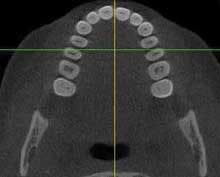

i-Cat 3-D Radiographic Imaging — Imaging Sciences has introduced compact cone beam computed tomography, which allows a three-dimensional analysis of bone structure and tooth orientation. This is helpful in implant planning as well as developmental or TMJ diagnosis. The 40-second scan is done with a unit resembling a pan/ceph unit and can provide cross sections of any location in the maxilla or mandible. Information is at www.imagingsciences.com